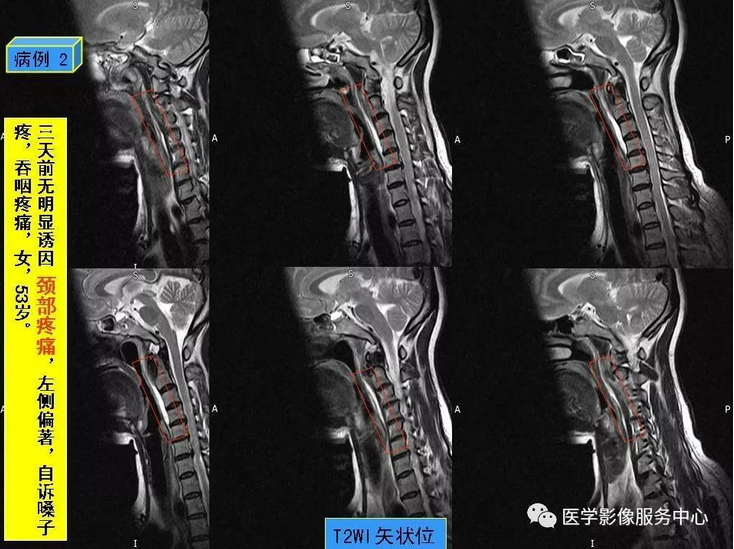

颈项疼痛是临床常见症状,最常见的原因就是颈椎病,包括颈椎骨质增生,颈椎间孔狭窄、颈间盘膨隆突出等表现,综合运用DR、CT、MRI这些影像检查方法,比较容易做出诊断,除此之外,引起颈项疼痛,还有比较少见的原因,不为影像诊断及临床医师所熟知,接下来我们看看下面的2个病例,比较少见的颈长肌肌腱炎。

颈长肌肌腱炎,是以颈项疼痛为主要临床表现的一种疾病,因颈长肌前方毗邻食道及咽部,常常伴发咽部疼痛和吞咽疼痛,临床及影像科医生对其认识较少,常易与其它引起颈项疼痛的疾病混淆 。

其病因为羟磷灰石结晶沉积于颈长肌上斜肌引起的炎性反应,以刺激组织渗出为主。羟磷灰石结晶沉积机制尚不十分明确,可能与损伤、组织坏死和炎症等因素相关。